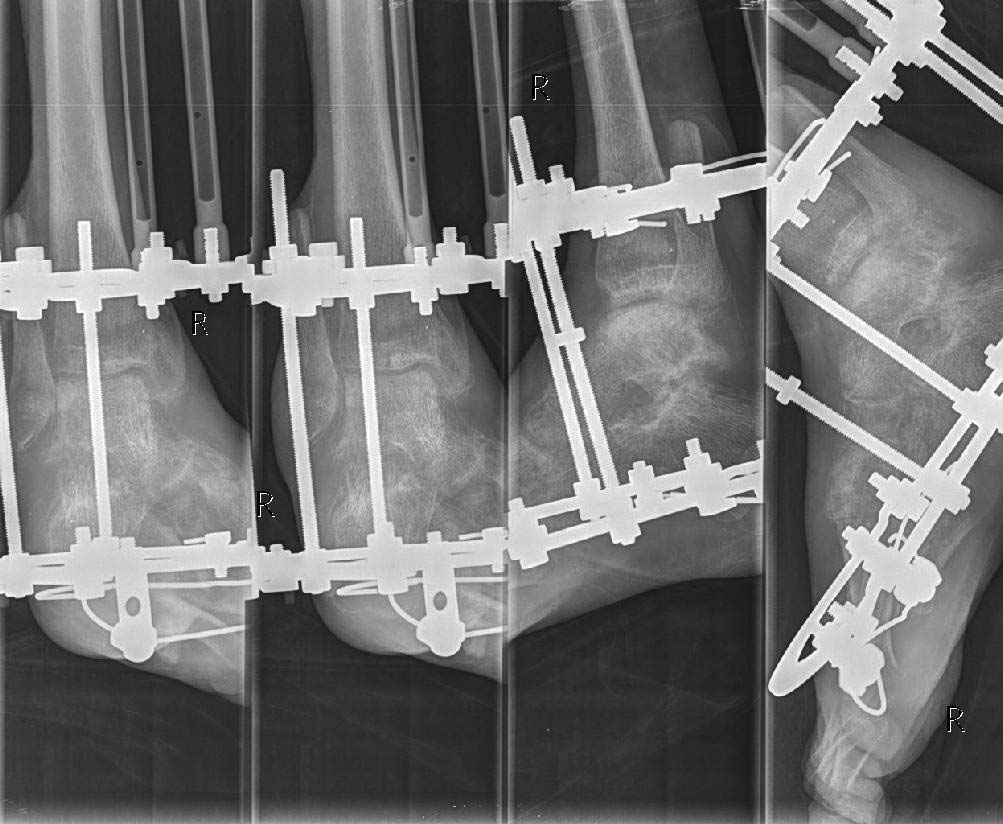

Имя     : 2015-02-20_212858-1.jpg

Url     : http://weborto.net:8080/pipermail/ortho/attachments/20150221/1b434c5b/attachment-0003.jpg

Вложение не в текстовом формате было извлечено…

Url     : http://weborto.net:8080/pipermail/ortho/attachments/20150221/1b434c5b/attachment-0004.jpg